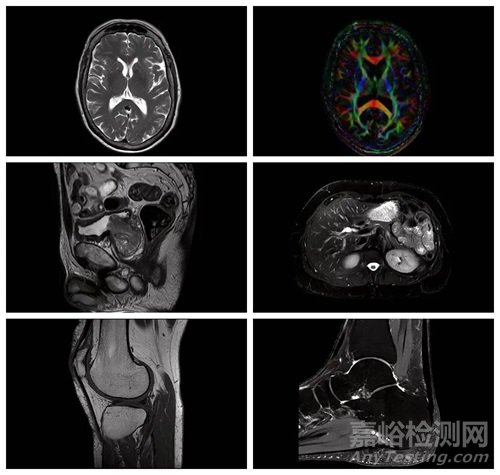

近日,西門子醫(yī)療3.0T全身磁共振Magnetom Cima.X獲批FDA。

這款產(chǎn)品被稱為西門子醫(yī)療的首款超強性能磁共振,早在2023年3月的歐洲放射學大會(ECR)上就曾展出,前不久也曾登陸上海,亮相第六屆進博會。其最大亮點是“雙子星”梯度系統(tǒng)(Gemini Gradients),最大梯度場強200mT/m,最大梯度切換率200T/m/s,比西門子醫(yī)療現(xiàn)有全身磁共振的最強梯度還要高2.5倍。

高梯度水平通過提高傳統(tǒng)MR掃描無法清晰看到的微觀結(jié)構(gòu)的可見性,能夠幫助臨床醫(yī)生更好地研究神經(jīng)退行性疾病。

MAGNETOM Cima.X搭載了AI驅(qū)動的圖像重建技術Deep Resolve,利用卷積神經(jīng)網(wǎng)絡來加快MRI掃描速度,包括Deep Resolve Gain、Sharp、Boost和Swift Brain,可將高分辨率MRI的掃描速度最多提高73%。